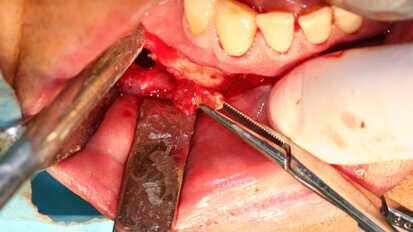

Naše zkušenosti s technikou kostní piezochirurgie po 15 letech klinického používání

Článek shrnuje osobní zkušenosti s kostní piezochirurgií po 15 letech používání v dentoalveolární chirurgii, implantologii a chirurgii ...